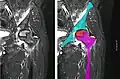

Front X-ray of right knee of an adolescent (epiphyseal plates are open): arrows point to avascular necrosis and developing osteochondritis dissecans in the outer medial condyle of femur

In the early stages, bone scintigraphy and MRI are the preferred diagnostic tools.[12]

X-ray images of avascular necrosis in the early stages usually appear normal. In later stages it appears relatively more radio-opaque due to the nearby living bone becoming resorbed secondary to reactive hyperemia.[2] The necrotic bone itself does not show increased radiographic opacity, as dead bone cannot undergo bone resorption which is carried out by living osteoclasts.[2]